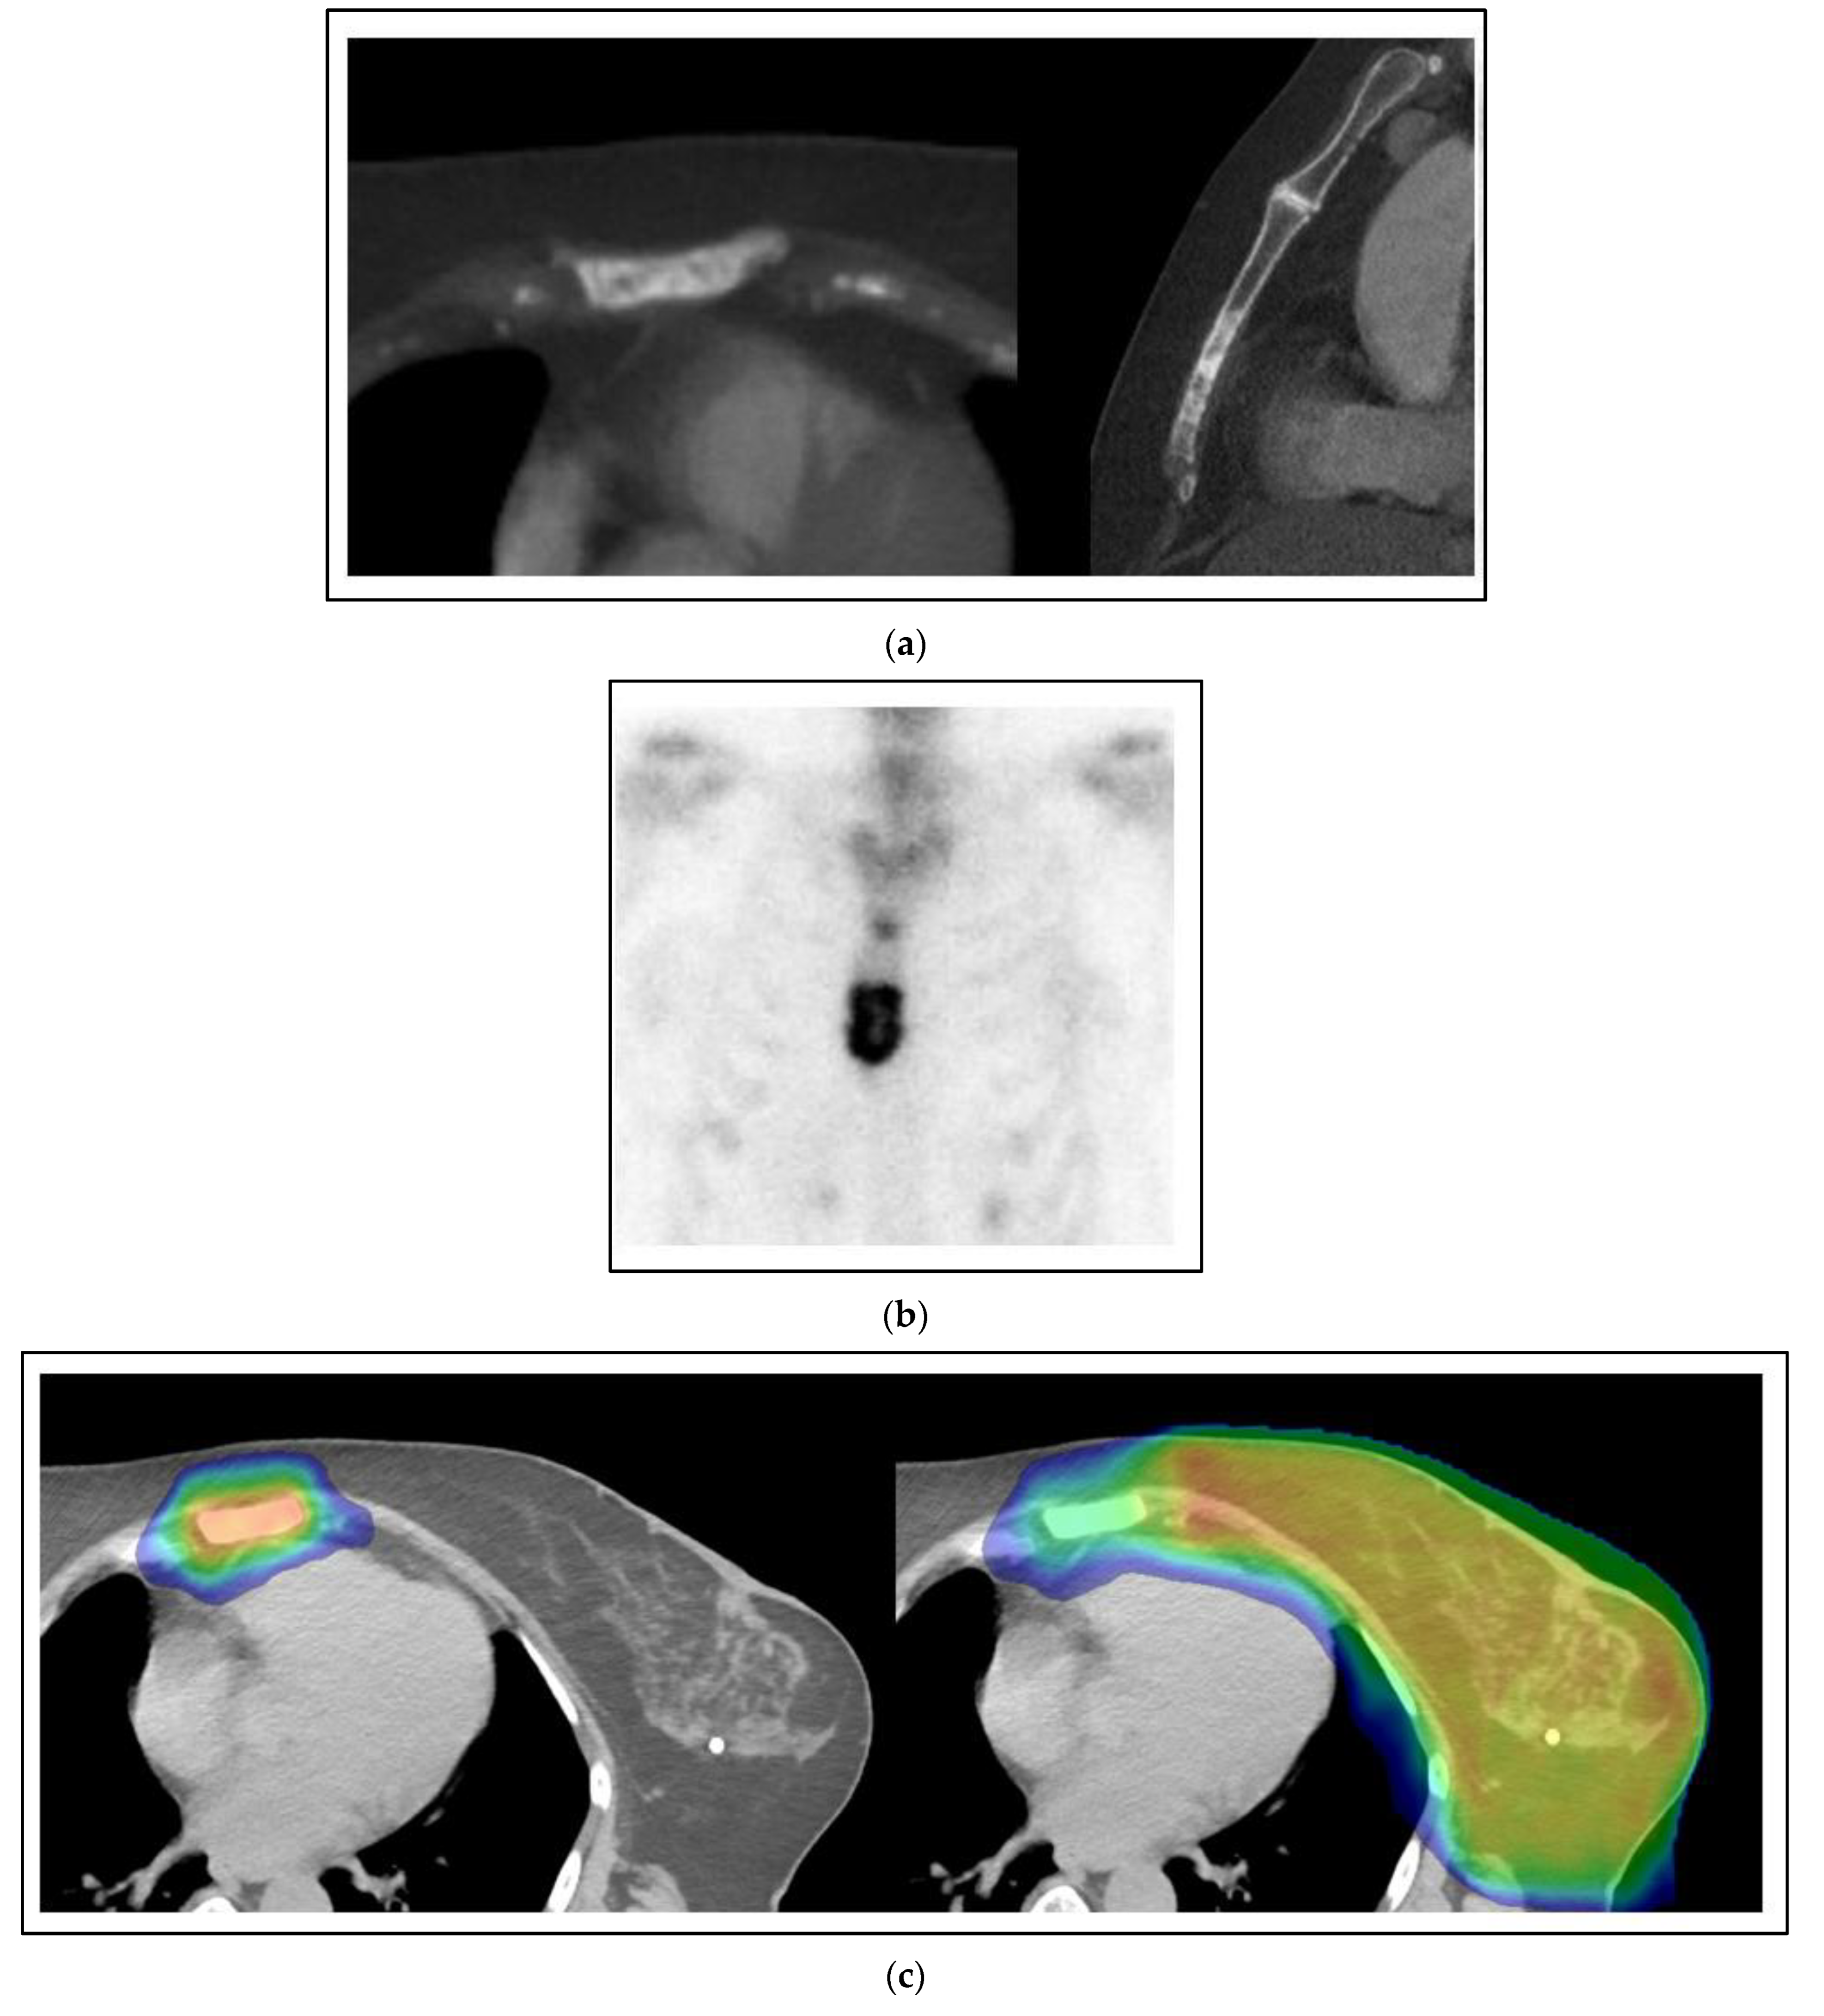

Figure 2 shows a case of a 60-year-old woman with the simultaneous presentation of left breast cancer involving the axillary and supraclavicular nodes with an oligometastasis of the sternum evident at the time of diagnosis. A biopsy of the axilla was positive for a grade 3 invasive carcinoma that was ER positive, PR positive and HER2 negative. Her staging for distant metastases was notable for a sclerotic lesion of the sternum on a CT that was positive on a bone scan. After neoadjuvant chemotherapy, an axillary dissection showed 2/14 nodes positive with pleomorphic invasive lobular carcinoma and extranodal extension. She was treated with comprehensive radiation to the left breast and regional nodes to a dose of 50 Gy with a boost to 66 Gy to the initially positive but undissected axillary and supraclavicular regions using external beam radiation. She concurrently had SBRT to the sternum 8 Gy × 5 fractions to 40 Gy. After radiation, she was treated with an aromatase inhibitor, cyclin-dependent kinase (CDK) 4 and 6 inhibitor, and zoledronic acid. She is without evidence of progression three years later.

Figure 2. Case 1: Simultaneous oligometastases. A 60-year-old woman presents with a locally advanced cancer of the left breast cT1N3M1 with an oligometastasis of the sternum. The sternal oligometastasis is shown on representative images from CT (a) and bone scan (b) imaging. (c) Radiation therapy to the left breast and sternum. The left image shows a colorwash image superimposed on a radiation planning CT of the dose from the sternum-directed SBRT given 40 Gy in 5 fractions, and the right image shows the colorwash of the dose of 50 Gy given to the breast and regional nodes combined with the sternal treatment. The yellow color indicates the prescribed dose of radiation, and the green and blue colors around the edges indicate the medium and lower dose fall-off of the radiation dose plan (d) The appearance on a CT scan image of the sternum 3 years after treatment. There is minimal residual sclerosis of the sternum with no evidence of progression.